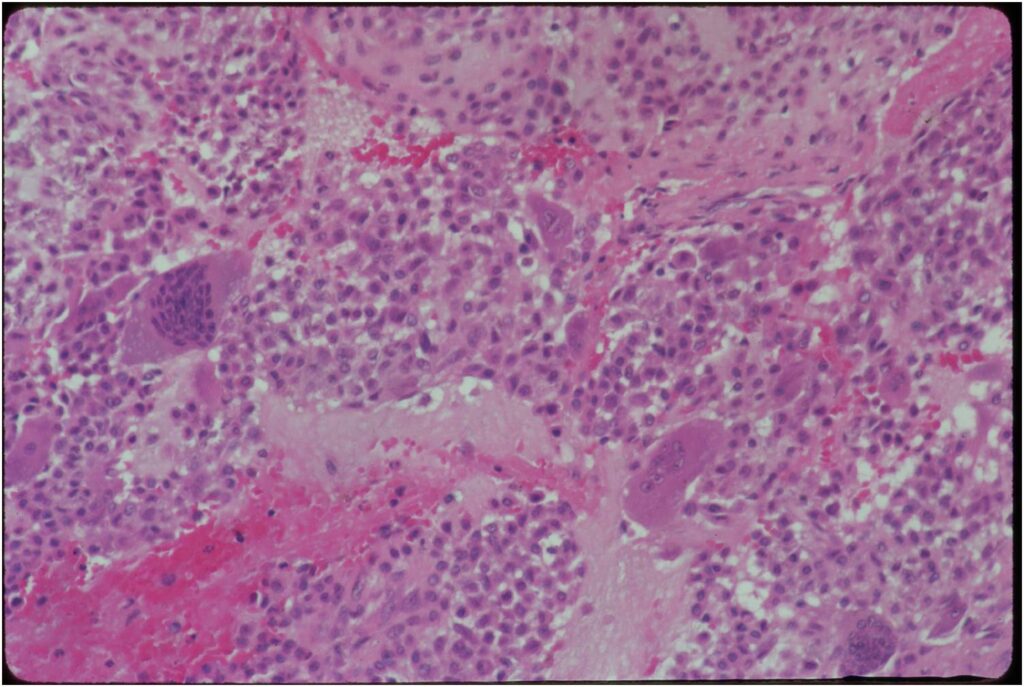

Gross Pathology

- Grossly variable appearance

- Grey/yellow/brown and gritty if has interspersed calcifications

- Interspersed red areas from hemorrhagic necrosis

- May be blue-grey areas from the chondroid matrix

- Rim of sclerotic bone is visible in totally resected specimens

- Lesion may be fully cystic with solid foci of tumor tissue at periphery

- May undergo aneurysmal bone cyst change (ABC change)

Specimen: Curettings

Microscopic Pathology

- Variable appearance depending on percentage of cells, necrosis, cartilage matrix formation and ABC change

- Chondroid matrix in up to 15% of tumor

- ABC component 5-15% of tumors

- The tumor is composed of chondroblasts that have a distinct, thick cell membrane. The thick cell membrane gives it a “Chicken Wire Fence Appearance,” especially when the cell membranes are calcified